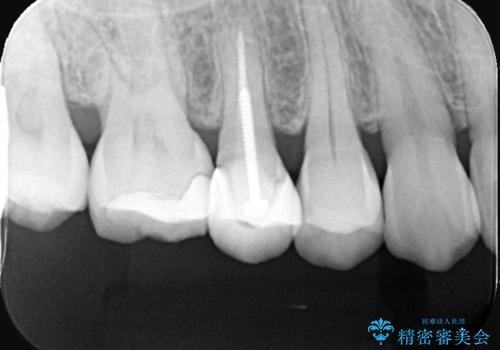

- 右上の奥歯(5番・6番)の被せ物の適合が悪く、歯ぐきが腫れやすい状態でした。患者さんご自身も「物がつまりやすい」「違和感がある」との訴えがあり、レントゲンと視診を行ったところ、被せ物の下にむし歯が進行していることが判明しました。特に右上5番は、神経の治療(根管治療)が過去に行われていましたが、根の先に炎症が残っており、治療のやり直しが必要と判断しました。

治療計画としては、まず古い被せ物を外し、虫歯の除去と右上5番の再根管治療を行った後、精密な形でセラミッククラウンを装着する方針としました。右上6番についても虫歯を除去し、必要な支台処置を行ったうえで同様にセラミッククラウンによる補綴を提案しました。

まずは両歯の古い被せ物を慎重に除去し、中のむし歯を確認しました。右上5番は神経の治療のやり直し(再根管治療)を行い、細菌感染を取り除いたうえで、根の中を密に封鎖しました。治療中は仮歯を入れて審美性と機能性を保ちつつ、歯ぐきの状態も改善していきました。